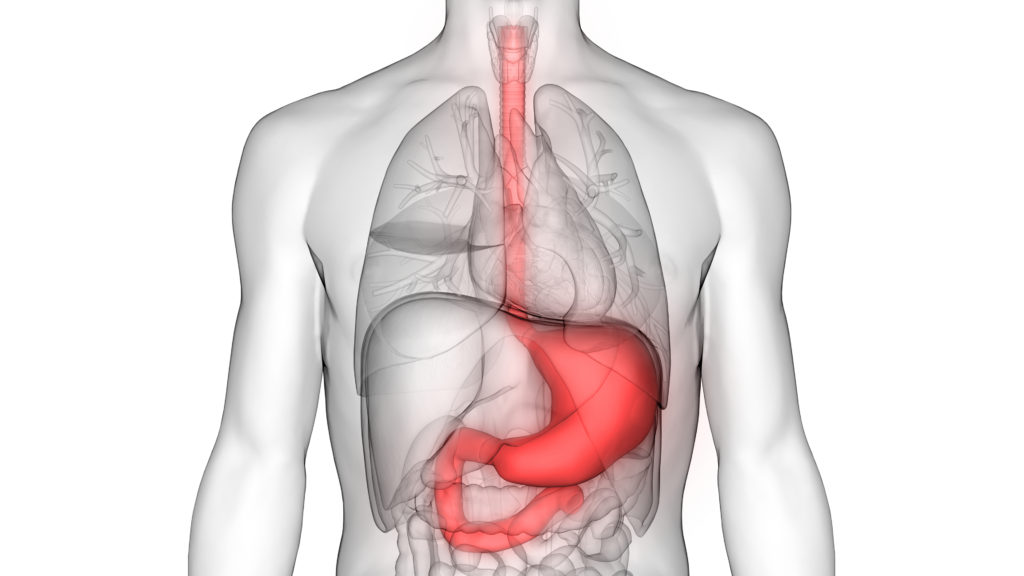

علاج جرثومة المعده نهائيا، جرثومة المعدة أو الملوية البوابية، هي عبارة عن بكتريا تؤدي إلى التهاب مزمن في المعدة والاثني عشر، وتعتبر سبب رئيسي للإصابة بالقرحة، حيث تعزو بطانة المعدة وتقوم بإنتاج مواد سامة بداخلها.

ينبغي الحرص على معالجة المرضى الذين تشير فحوصاتهم إلى نتائج إيجابية للإصابة بجرثومة المعدة، كما يجب التأكيد على استكمالهم للخطة العلاجية الموصوفة، والتعرف على الأعراض الجانبية المصاحبة للأدوية المعالجة، يتم التخلص من جرثومة المعدة عن طريق العلاج الثلاثي أو الرباعي.